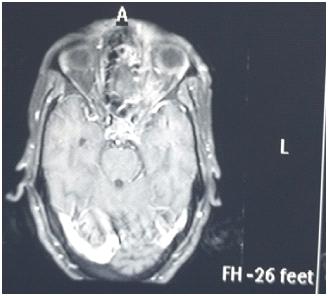

Among the metabolically abnormal patient’s population 20% (n=3) had Hypoglycemia, 40%(n=6) presented with Dyselectrolytemia, 26.67% (n=4) had Uremia, 13.33% (n=2) presented with Hepatic encephalopathy. Overall, 31 patients underwent Lumber puncture, of which CSF report shows abnormality in 11 (35.48%) cases and normal in 20 patients (64.51%). Abnormal CSF report suggesting viral meningoencephalitis found in 46% (n=5), bacterial meningitis in18% (n=2), Tuberculous Meningitis in 27% (n=3), Aseptic meningitis in 9% (n= 1). All 65 subjects underwent CT scan brain among which MRI Brain also done in 55 cases. CT findings is normal in 44.62% (n=29), abnormal in 55.38% (n=36). The most common CNS lesion on CT scan was infarction in 10.77% followed by ring lesion in 9.23% and intracerebral Hemorrhage in 7.96%. We observed cerebral infarction is causative factor of Seizure in female (15%) but intracerebral hemorrhage and ring lesion are most common findings in male, comprising 11.11% patients at each category. The CT scan in new onset Seizure of elderly patient population revealed Infarction in 28.57%, Gliosis in 19.04% and cerebral atrophy in 14.28%. The breakup of findings in MRI Scan of 55 patients shows Hyperintensities on T2, indicating Demyelination / Inflammation/edema in12.31% followed by infarction in 10.77% and ring lesion in 9.23%. In the female population, hyperintensities on T2 MRI found in 15% and Infarction in 15% whereas among the males intracerebral Hemorrhage, Ring lesion and hyperintensities on T2 found at similar occurrence rate @11% in each of these three types of lesions. EEG was done on 80% patients (n=52) of whom 22 patients has abnormal discharge in EEG but 30 patients have normal presentation. Among 65 patients one female expired due to Acute Demyelinated Encephalomyelitis (ADEM) and two males expired one due to Hemorrhage, another one with CNS infection when undergoing treatment indoor.

We found a strong positive correlation between abnormal EEG and abnormal Neuroimaging with Correlation coefficient of 0.902, (P- Value 0.0138) but almost no correlation found between normal EEG with normal Neuroimaging (Figs 1-4).

About 23% of patients with adult onset first seizure has metabolic derangement and the most common etiology was Dyselectrolytemia. The most common Central Nervous System (CNS) Infection as detected by CSF study was viral meningoencephalitis followed by Tuberculous Meningitis. The most common CNS lesion detected by CT studies as well as by MRI Brain was infarction and ring lesion, the two Neuroimaging studies corroborated in 75.38% of Seizure patients. Abnormal discharge in EEG found in34% cases. In majority patients EEG report was normal. EEG abnormality was more common in patients with Focal Seizure rather than GTCS patients. Thus, the most common etiology of first Seizure onset at adult age over 18 years were metabolic derangements (16.92%), CNS Infection or Inflammation (15.38%) and intracerebral Space occupying lesion (15.38%), usually ring lesion, tumors and Metastasis. Idiopathic Seizure found in 7.69% patients. The Correlation between abnormal Neuroimaging and abnormal EEG is strongly positive and statistically significant (P -Value = 0.013) but the same is not true in cases of normal Neuroimaging and normal EEG findings.